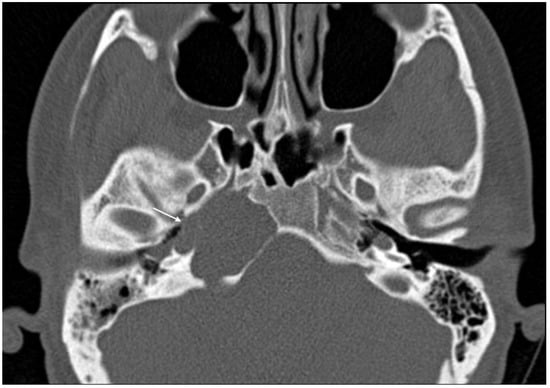

Imaging data from each patient were examined by an expert radiologist and an ENT specialist focusing attention not only on the location of the cyst, but also on the adjacent structures involved. Considering the available literature on symptoms and hypothesized regions of radiological involvement, we established a reproduceable pre-operative radiologic map to better correlate typical symptoms, such as headache, hearing loss, vestibular symptoms, tinnitus, otitis media, diplopia, and facial paresthesia, with PACG. The following regions were considered: (1) temporal lobe/posterior fossa compression (Figure 1); (2) Meckel’s cave compression (Figure 1); (3) Eustachian tube compression/erosion (Figure 2); (4) internal auditory canal erosion (Figure 3); (5) cochlear basal turn erosion (Figure 4); (6) Dorello canal involvement (Figure 5); (7) jugular tubercle erosion. The latter parameter was introduced to evaluate its possible correlation with an atypical clinical presentation, namely fainting. To standardize all these radiological examinations, the jugular tubercle was defined in axial sections as the bony convexity medial to the jugular foramen just above the hypoglossal canal; in coronal sections, it is the bony part directly above the hypoglossal canal (Figure 6).

Figure 6. CT scan in the axial (A) and coronal (B) planes of the jugular tubercle (white arrow) defined as the bony convexity medial to the jugular foramen just above the hypoglossal canal (in axial sections) or the bony part just above the hypoglossal canal (in coronal sections).